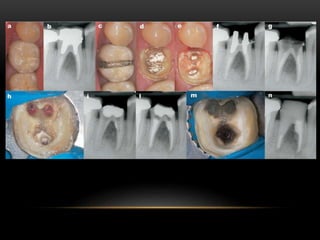

• The tip of an ultrasonic unit (Fig.

2h) is then applied to the side of

the post fragment at full power

with water irrigation.

• Ultrasonic vibration is applied for

periods of a few seconds

followed by drying with

compressed air. This should lead

to dislodgement of the fragment

of the post, which can then be

removed with a fine forceps